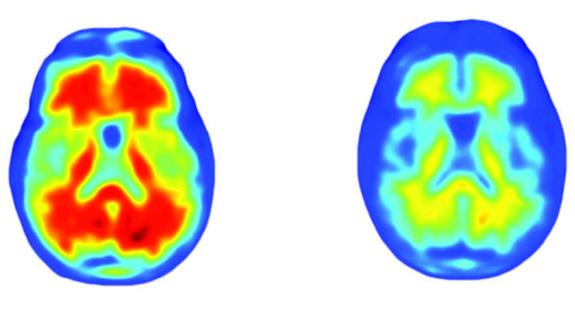

Un equipo internacional de investigadores ha presentado Aducanumab, un fármaco experimental que en su primer ensayo exploratorio ha logrado detener el deterioro de la memoria y la capacidad cognitiva asociados al Alzheimer. El medicamento, todavía en fase de pruebas, está diseñado para eliminar unas placas que se acumulan en el cerebro de los pacientes de esta enfermedad y que los investigadores creen que pueden ser su desencadenante. Si estos resultados se confirman en experimentos más amplios, podría convertirse en el primer tratamiento capaz de prevenir y detener el avance de una de las dolencias neurodegenerativas más comunes y, a la vez, que más han desafiado a la ciencia médica.

Desde hace más de dos décadas, muchos científicos creen que el fenómeno que desencadena el Alzheimer es la acumulación en el cerebro de unas pequeñas proteínas denominadas ß-amiloide. Aducanumab, afirmó Roger A. Nitsch, director del Instituto de Medicina Regenerativa de la Universidad de Zurich (Suiza) y co-coordinador del trabajo, que ha publicado este miércoles la revista 'Nature', es un anticuerpo que ha mostrado la capacidad de eliminar estas placas. En un ensayo clínico con 165 pacientes, los investigadores han visto que cuando se inocula este fármaco, las placas desaparecen. Y que, además, el ritmo de desaparición aumenta con la dosis usada.

Aun así, los experimentos que han llevado a cabo han sido todos con pacientes confirmados de Alzheimer. Todos, por tanto, con síntomas y con muchísimas ß-amiloide acumuladas en el cerebro. Pese a esto, su eliminación parece que frena el avance de los síntomas de la enfermedad. En una prueba estándar para medir el deterioro de la capacidad cognitiva denominada Clasificación Clínica de la Demencia (CDR), los pacientes que recibieron el tratamiento con Aducanumab dejaron de empeorar. «Durante el primer medio año de tratamiento todos empeoraron, como era de esperar, y según el curso normal de la enfermedad», explicó Nitch. «Pero en los seis meses siguientes, los pacientes que no estaban tomando placebo básicamente se estabilizaron».